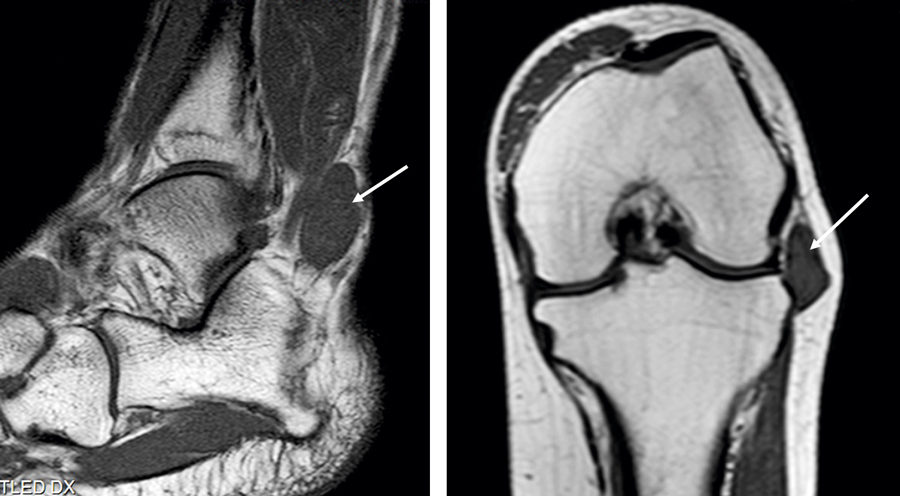

Figur 1 och 2. Magnetisk resonanstomografi av laterala malleolen hos patient 1 (till vänster) samt knäleden hos patient 2 (till höger). Bedömningen blev hos båda patienterna initialt ganglion, men det visade sig sedan handla om synovialt sarkom.

Vid läkarbesök två månader senare bedömdes resistensen vara ett tydligt ganglion dorsalt om laterala malleolen, lätt ömmande vid palpation. Patienten sattes på väntelista för dagkirurgisk exstirpation, vilken gjordes en dryg månad senare. Överläkaren som skulle operera valde i stället att punktera resistensen på »ganglieinnehåll« och sprutade kortison i den. Resistensen försvann helt, men området var fortfarande något ömt. Tre veckor senare hade knölen recidiverat, och en MR-undersökning beställdes. Denna visade en subkutan, multilobulär, cystisk bildning, 2,5 × 3 × 1,5 cm stor, vid platsen för peroneussenorna. Bedömningen blev återigen ganglion (Figur 1). Resistensen exciderades i narkos men skickades inte för PAD.

En i övrigt frisk 25-årig kvinna sökte ortopedmottagningen på ett länssjukhus för smärta lateralt i höger knä. En MR-undersökning utfördes och påvisade en liten resistens subkutant, lateralt om knäleden. MR-bilderna länkades till Sarkomcentrum i Stockholm för sekundärgranskning. Den radiologiska bedömningen där blev sannolikt meniskganglion (Figur 2). Trots insatt fysioterapi och NSAID utvecklade hon en smärtsam kontraktur i knäleden. Tillståndet bedömdes som ett komplext regionalt smärtsyndrom (CRPS) och hon remitterades till smärtmottagning.